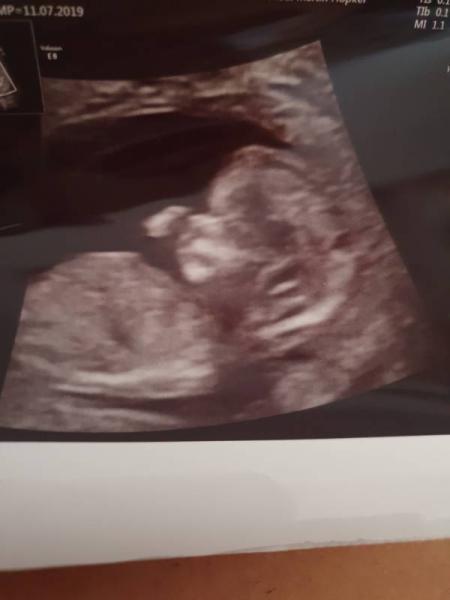

Leider noch kein Outing,Baby wollte sich nicht so zeigen . Nackenfalte ist bei 1.5mm und alles unauffällig. Das Herz hat fleißig geschlagen und es hat so toll gezappelt Hab ein Video gemacht und auch die Herztöne durfte ich hören . Es war ein sehr schöner Termin. Für das Foto hat er heute lange gebraucht da minimi nicht fotogen war heute

Bild zu Zurück vom Termin  - Forum für April - Mamis